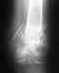

Решиться на операцию очень сложно. Я сейчас думаю, убирать или не убирать стержень из бедра... Увидела обсуждение и хочу о своем суставе рассказать. Был послетравматический артроз голеностопного сустава. Не сильно болел, но после того как набрала вес боли резко усилились. И даже снижение веса не помогло. Ходить не могла. Обратилась в свою больницу по месту жительства.

Травматологи предложили закрыть сустав. Консульторовалась в разных клиниках. В том числе и в Израиле. Мнения разделись. В центрах, где много занимаются операциями на стопе, рекомендовали эндопротез. Говорили про риск, что нельзя вес набирать. ГОд назад съездила на операцию в Москву. Оперировал Коробушкин Г. Операция прошла успешно. Через полтора месяца ходила и на ступала. Стопа гнется. Не болит.